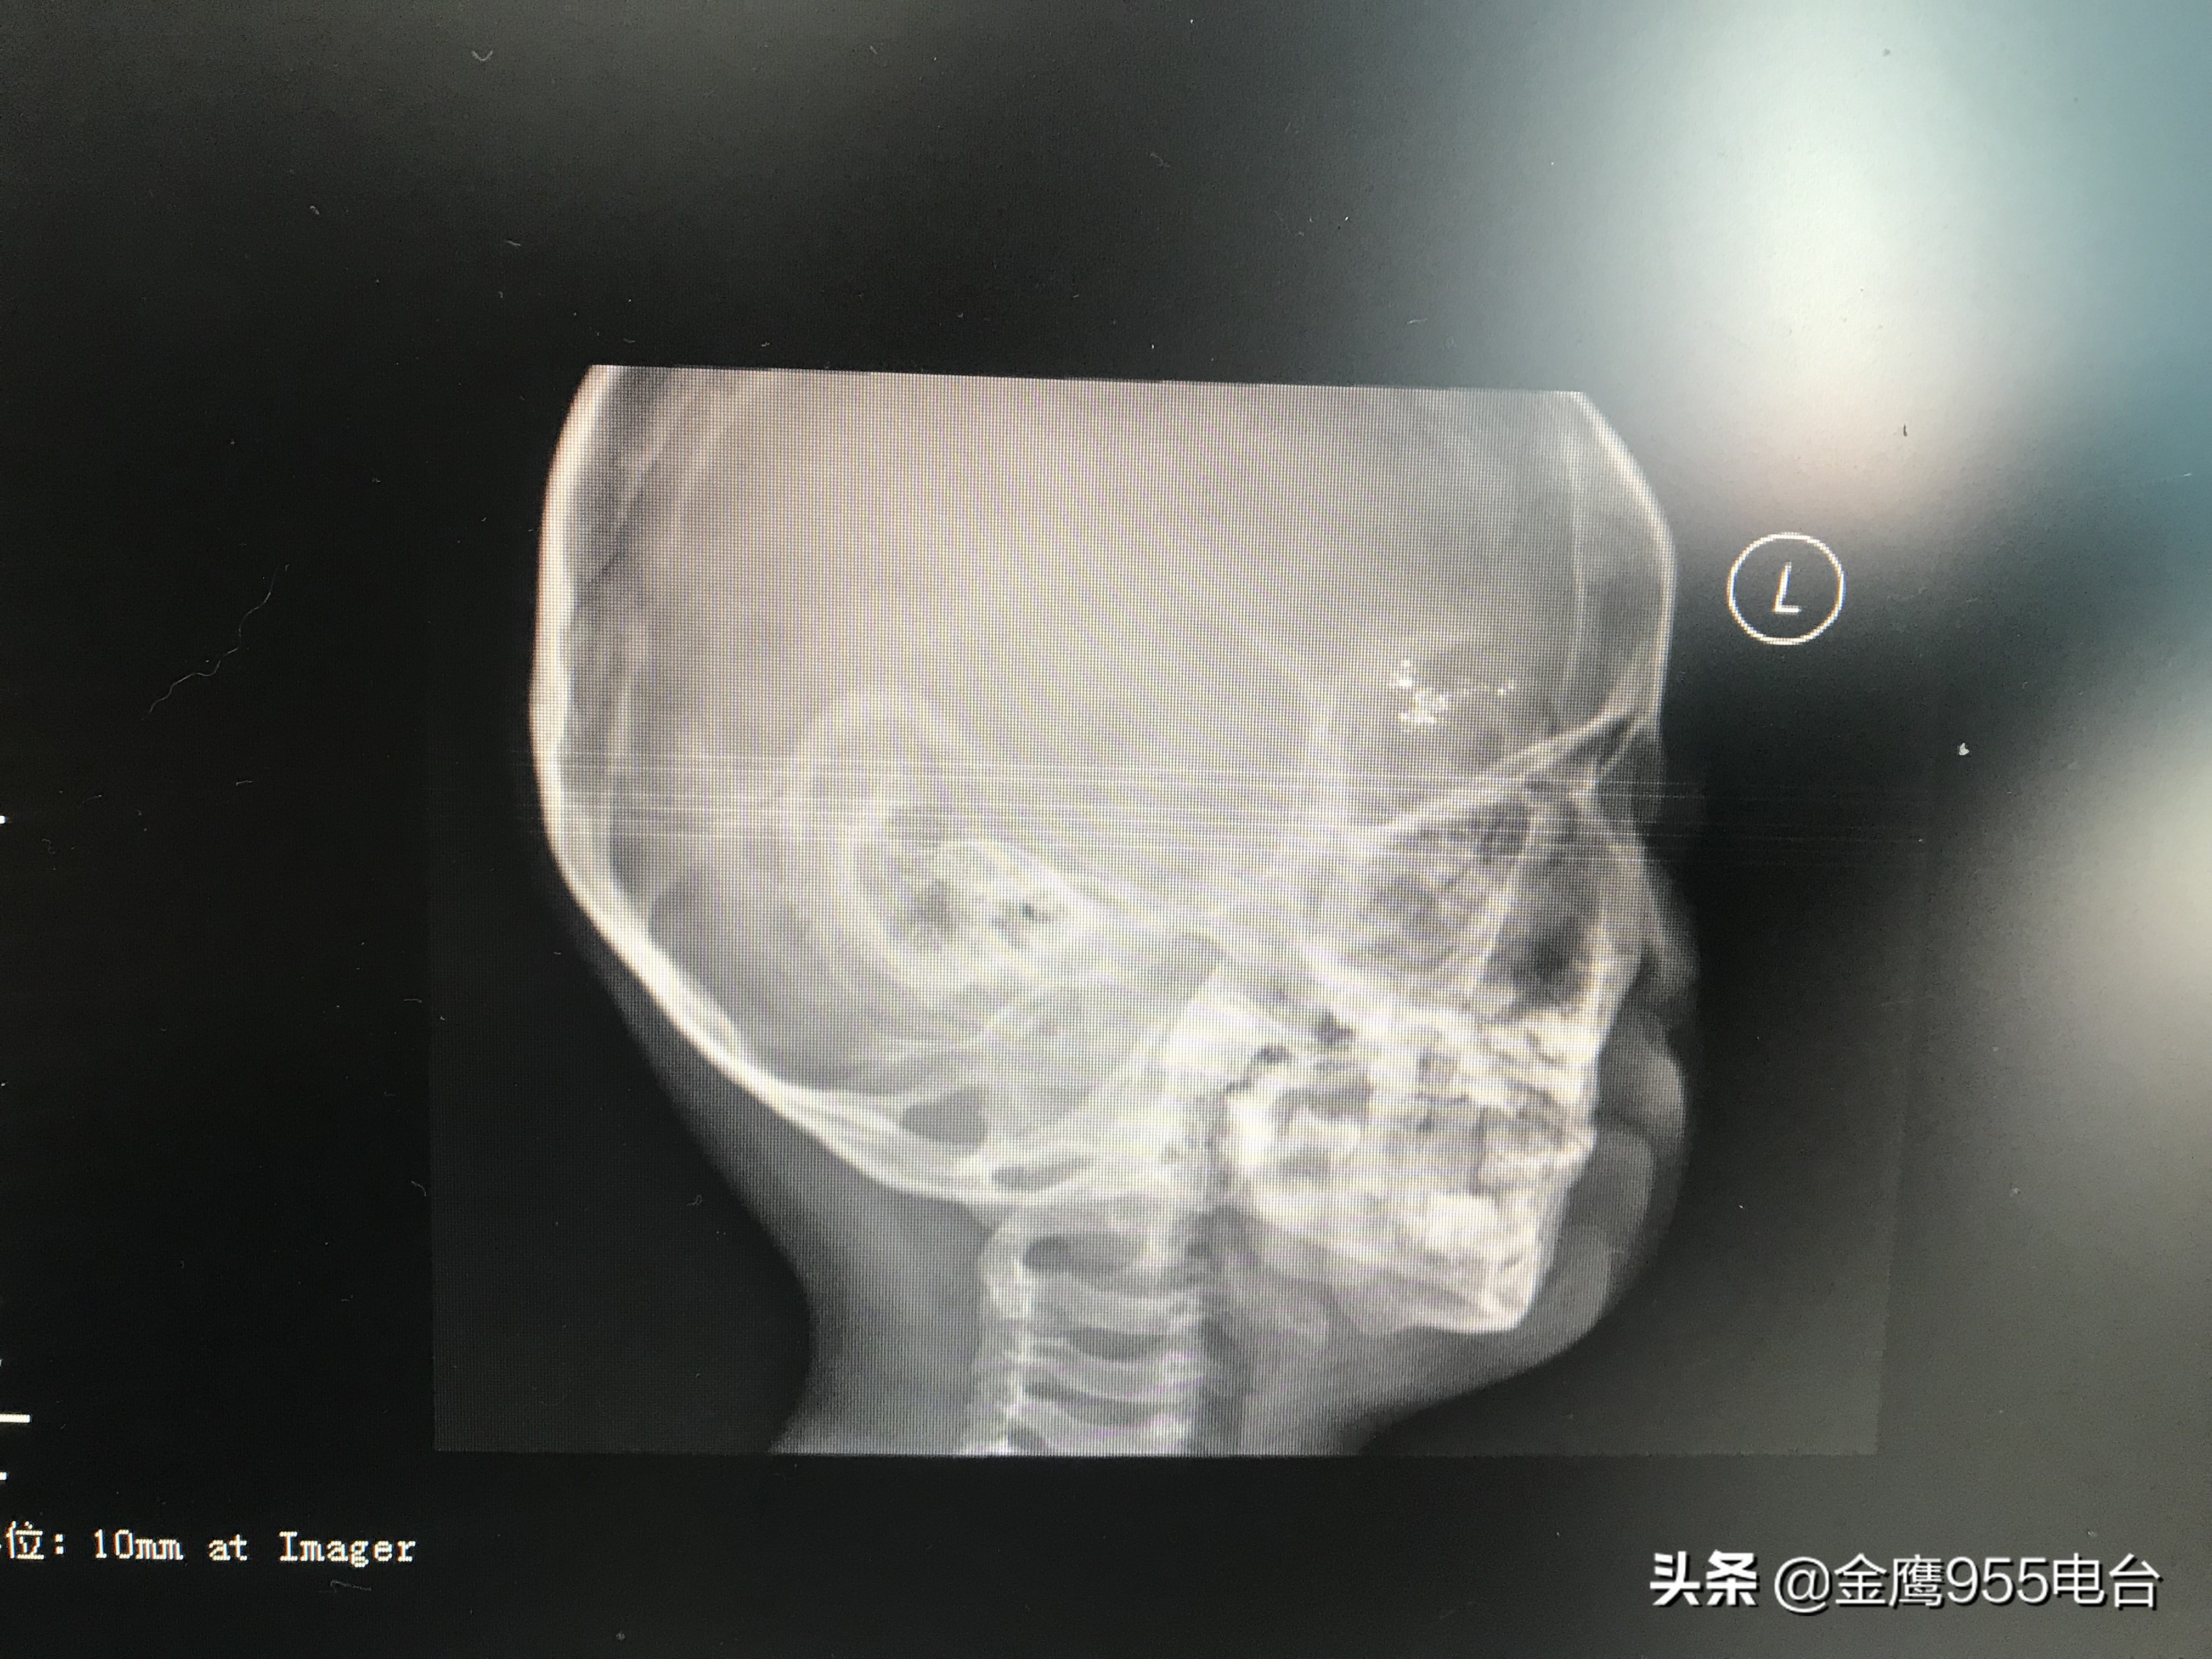

“这是他的颅脑CT,可以看到还是有一个高密度的阴影,如果这个汞珠不取出来的话,会对小孩的中枢神经发育、肾脏、性格方面都有影响。比如这个小孩,已经出现好动,有攻击性的行为。”湖南省职业病防治院职业病一科副主任医师袁娟告诉记者,正常人体内的尿汞含量在4微克每克肌酐左右,然而小智体内的尿汞含量最高达到了737微克每克肌酐,超过正常水平近两百倍。由于汞珠残留的位置靠近颅脑,不能够通过手术直接将残留在小智体内的汞珠取出。最终医院决定,利用药物加速汞珠的自由排出过程。经过三年的驱汞治疗,小智的尿汞含量已经下降到了正常人体水平的四十倍左右。